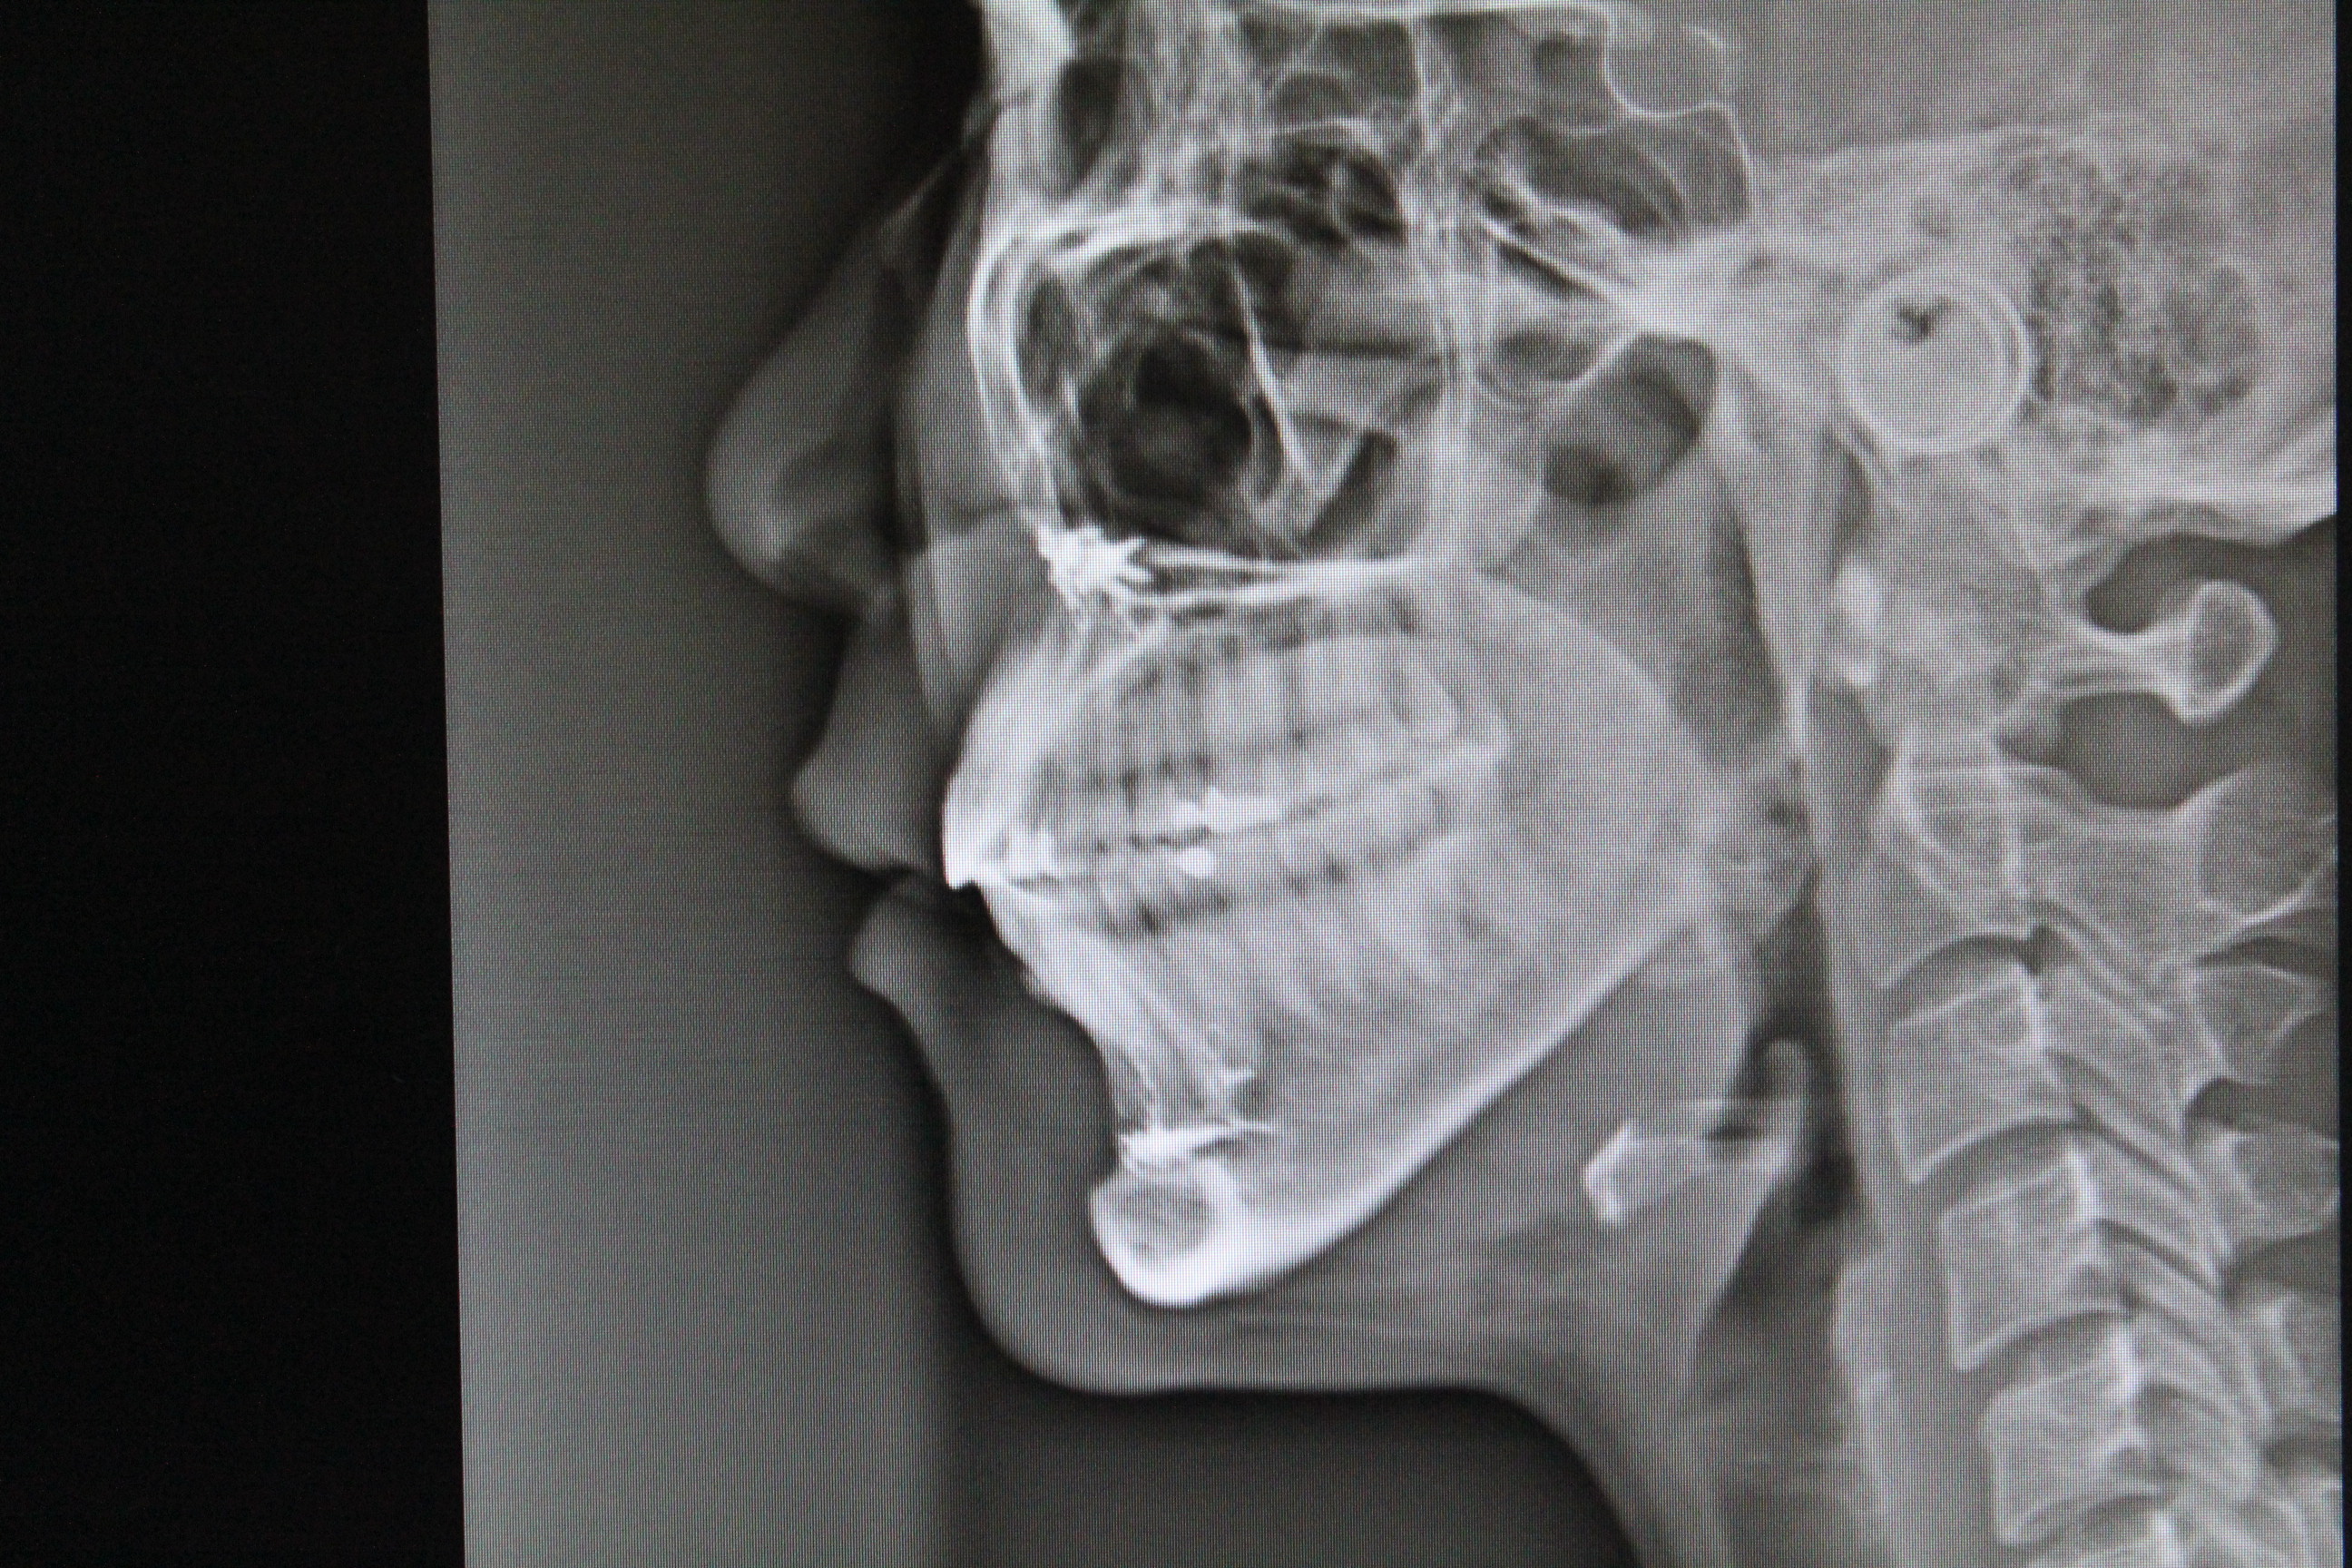

수술전 - 측면 엑스레이

수술후 - 측면 엑스레이